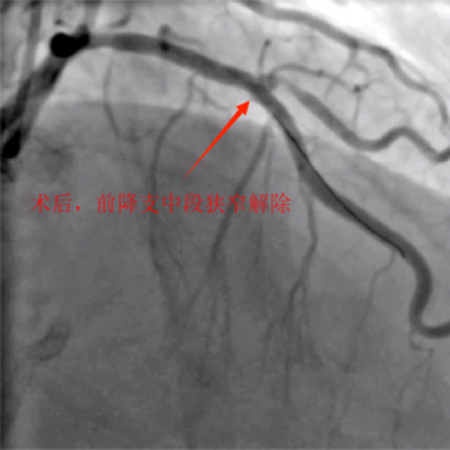

造影可见:前降支中段发出对角支后极重度狭窄,可见侧支循环右冠中远端,回旋支发出钝缘支后闭塞,可见钝缘支侧支循环回旋支远端;右冠中段闭塞。

11月5日,患者各方面情况相对稳定,口服双联抗血小板聚集药物消化道反应也无异常。综合评估后再次为患者行冠脉介入治疗。术前我把老吴左右手都消毒了,左手备用,可能需要双侧造影辅助开通右冠。术中顺利开通右冠闭塞血管并植入支架恢复正常血流,同期解决前降支极重度狭窄病变并植入支架解除危机。手术总用时1小时40分钟,造影剂用量120ml,手术很顺利,比预想的效果要好,已经超预期完成。